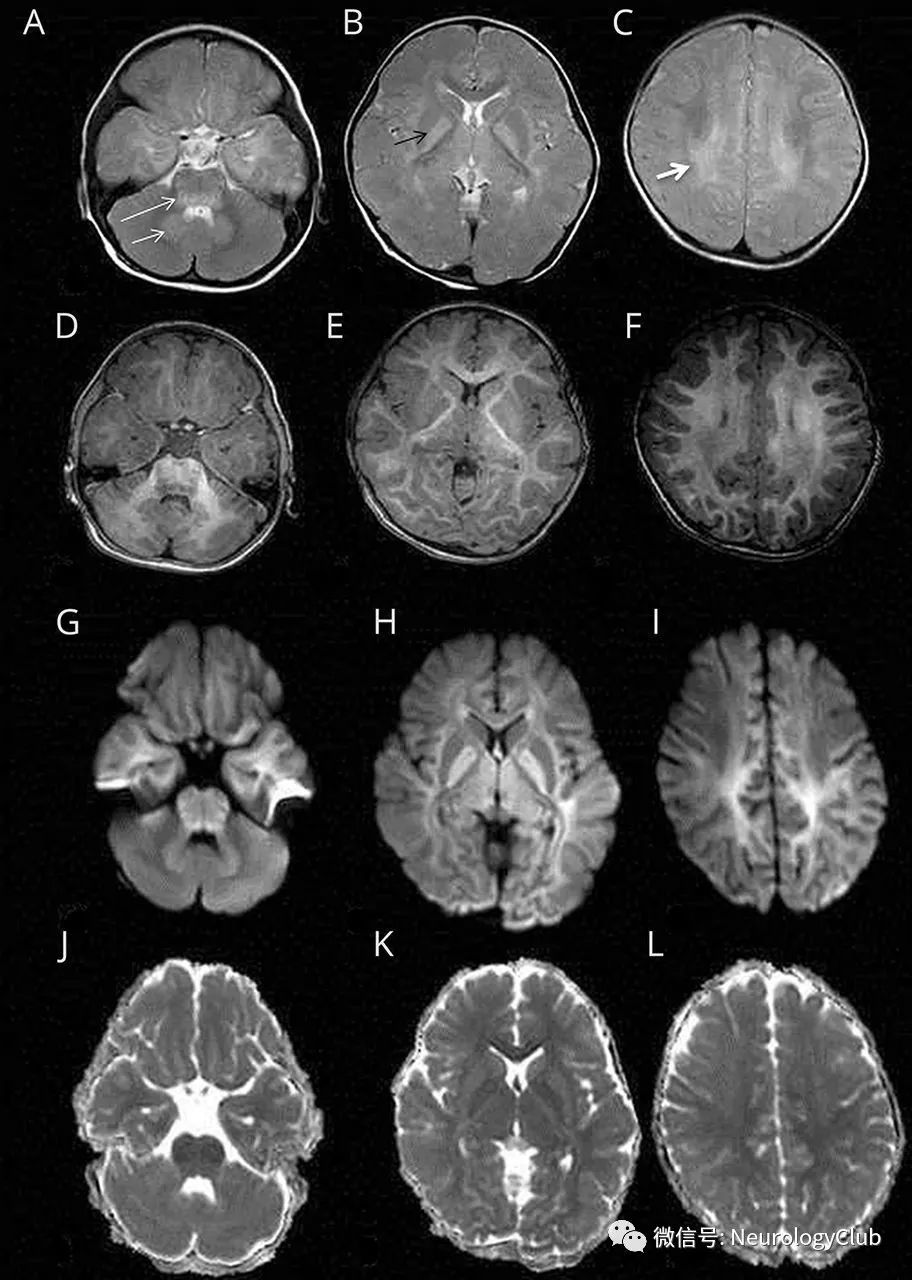

影像挑战:3岁女孩,发作性共济失调

图片尺寸912x1280

11个案例助你掌握艾滋病相关七大类颅内感染影像学表现

图片尺寸640x769